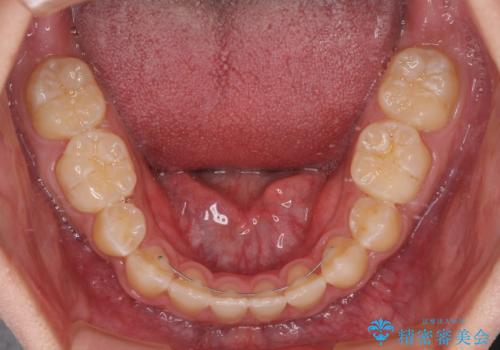

口元の突出感を改善 受け口傾向の咬み合わせの抜歯矯正

下顎の残存乳歯は小臼歯よりも大きいため、スペースを閉じるために長い期間を必要としますが、予想通りに長期間を要することとなりました。

受け口傾向の方の抜歯矯正は、下顎前歯が舌側に倒れることで歯肉退縮を起こしやすいことが知られていますが、ワイヤーに工夫をすることでリスクを軽減させています。